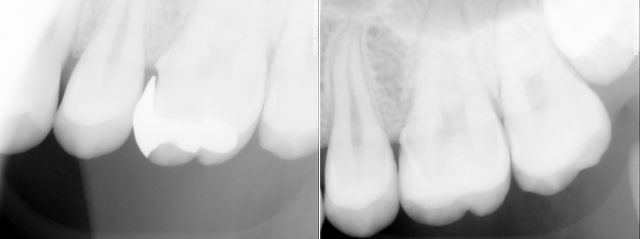

左上の銀歯をオールセラミックで治療しました。

その時のレントゲン写真です。銀歯の時は歯との隙間がずいぶん大きい事がわかります。セラミックインレーに変えて歯との隙間もなくなり、今後はいい状態が保てます。